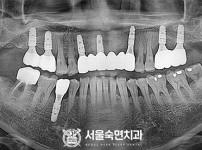

임플란트-전후사진4

치과를-선택할-때-꼭-확인하세요-서울숙면치과-임플란트-전후사진